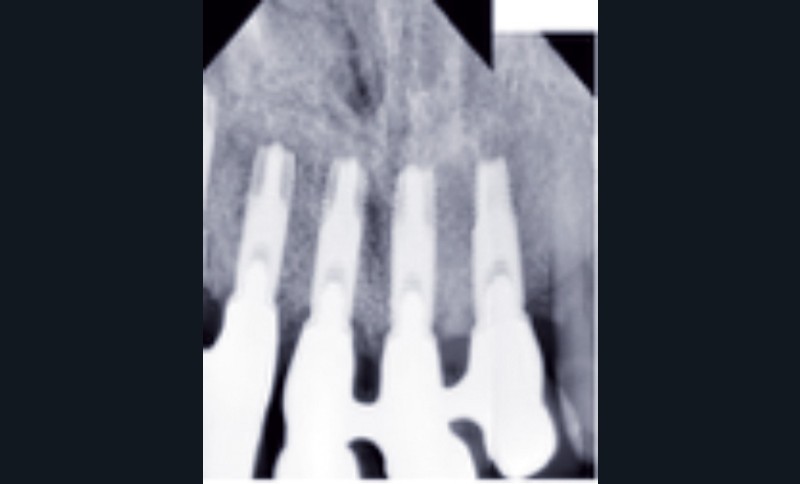

Cette partie de la présentation ne se contentait pas de rapporter les principes précédemment décrits à des régions limitées des maxillaires mais étendait la discussion à la difficulté majeure rencontrée en implantologie : rattraper des erreurs de positionnement implantaire ayant entraîné des compromis prothétiques inesthétiques. La solution thérapeutique mise en œuvre par Benoît Philippe consiste à appliquer la procédure d’ostéotomie segmentaire à l’entité constituée par l’os alvéolaire péri-implantaire et les implants. Les couronnes implantaires sont déposées. Le tracé d’ostéotomie encadre le segment à repositionner mais n’implique pas la corticale palatine qui sera fracturée pour éviter toute lésion du périoste (nourricier du segment alvéolo-implantaire). Un dispositif prothétique préparé en amont guide la translation du fragment qui est fixé au moyen de plaque d’ostéosynthèse dans la situation idéale. Le capital squelettique est reconstruit et l’espace prothétique disponible est normalisé.

La procédure chirurgicale du cas est à visionner sur : www.idweblogs.com